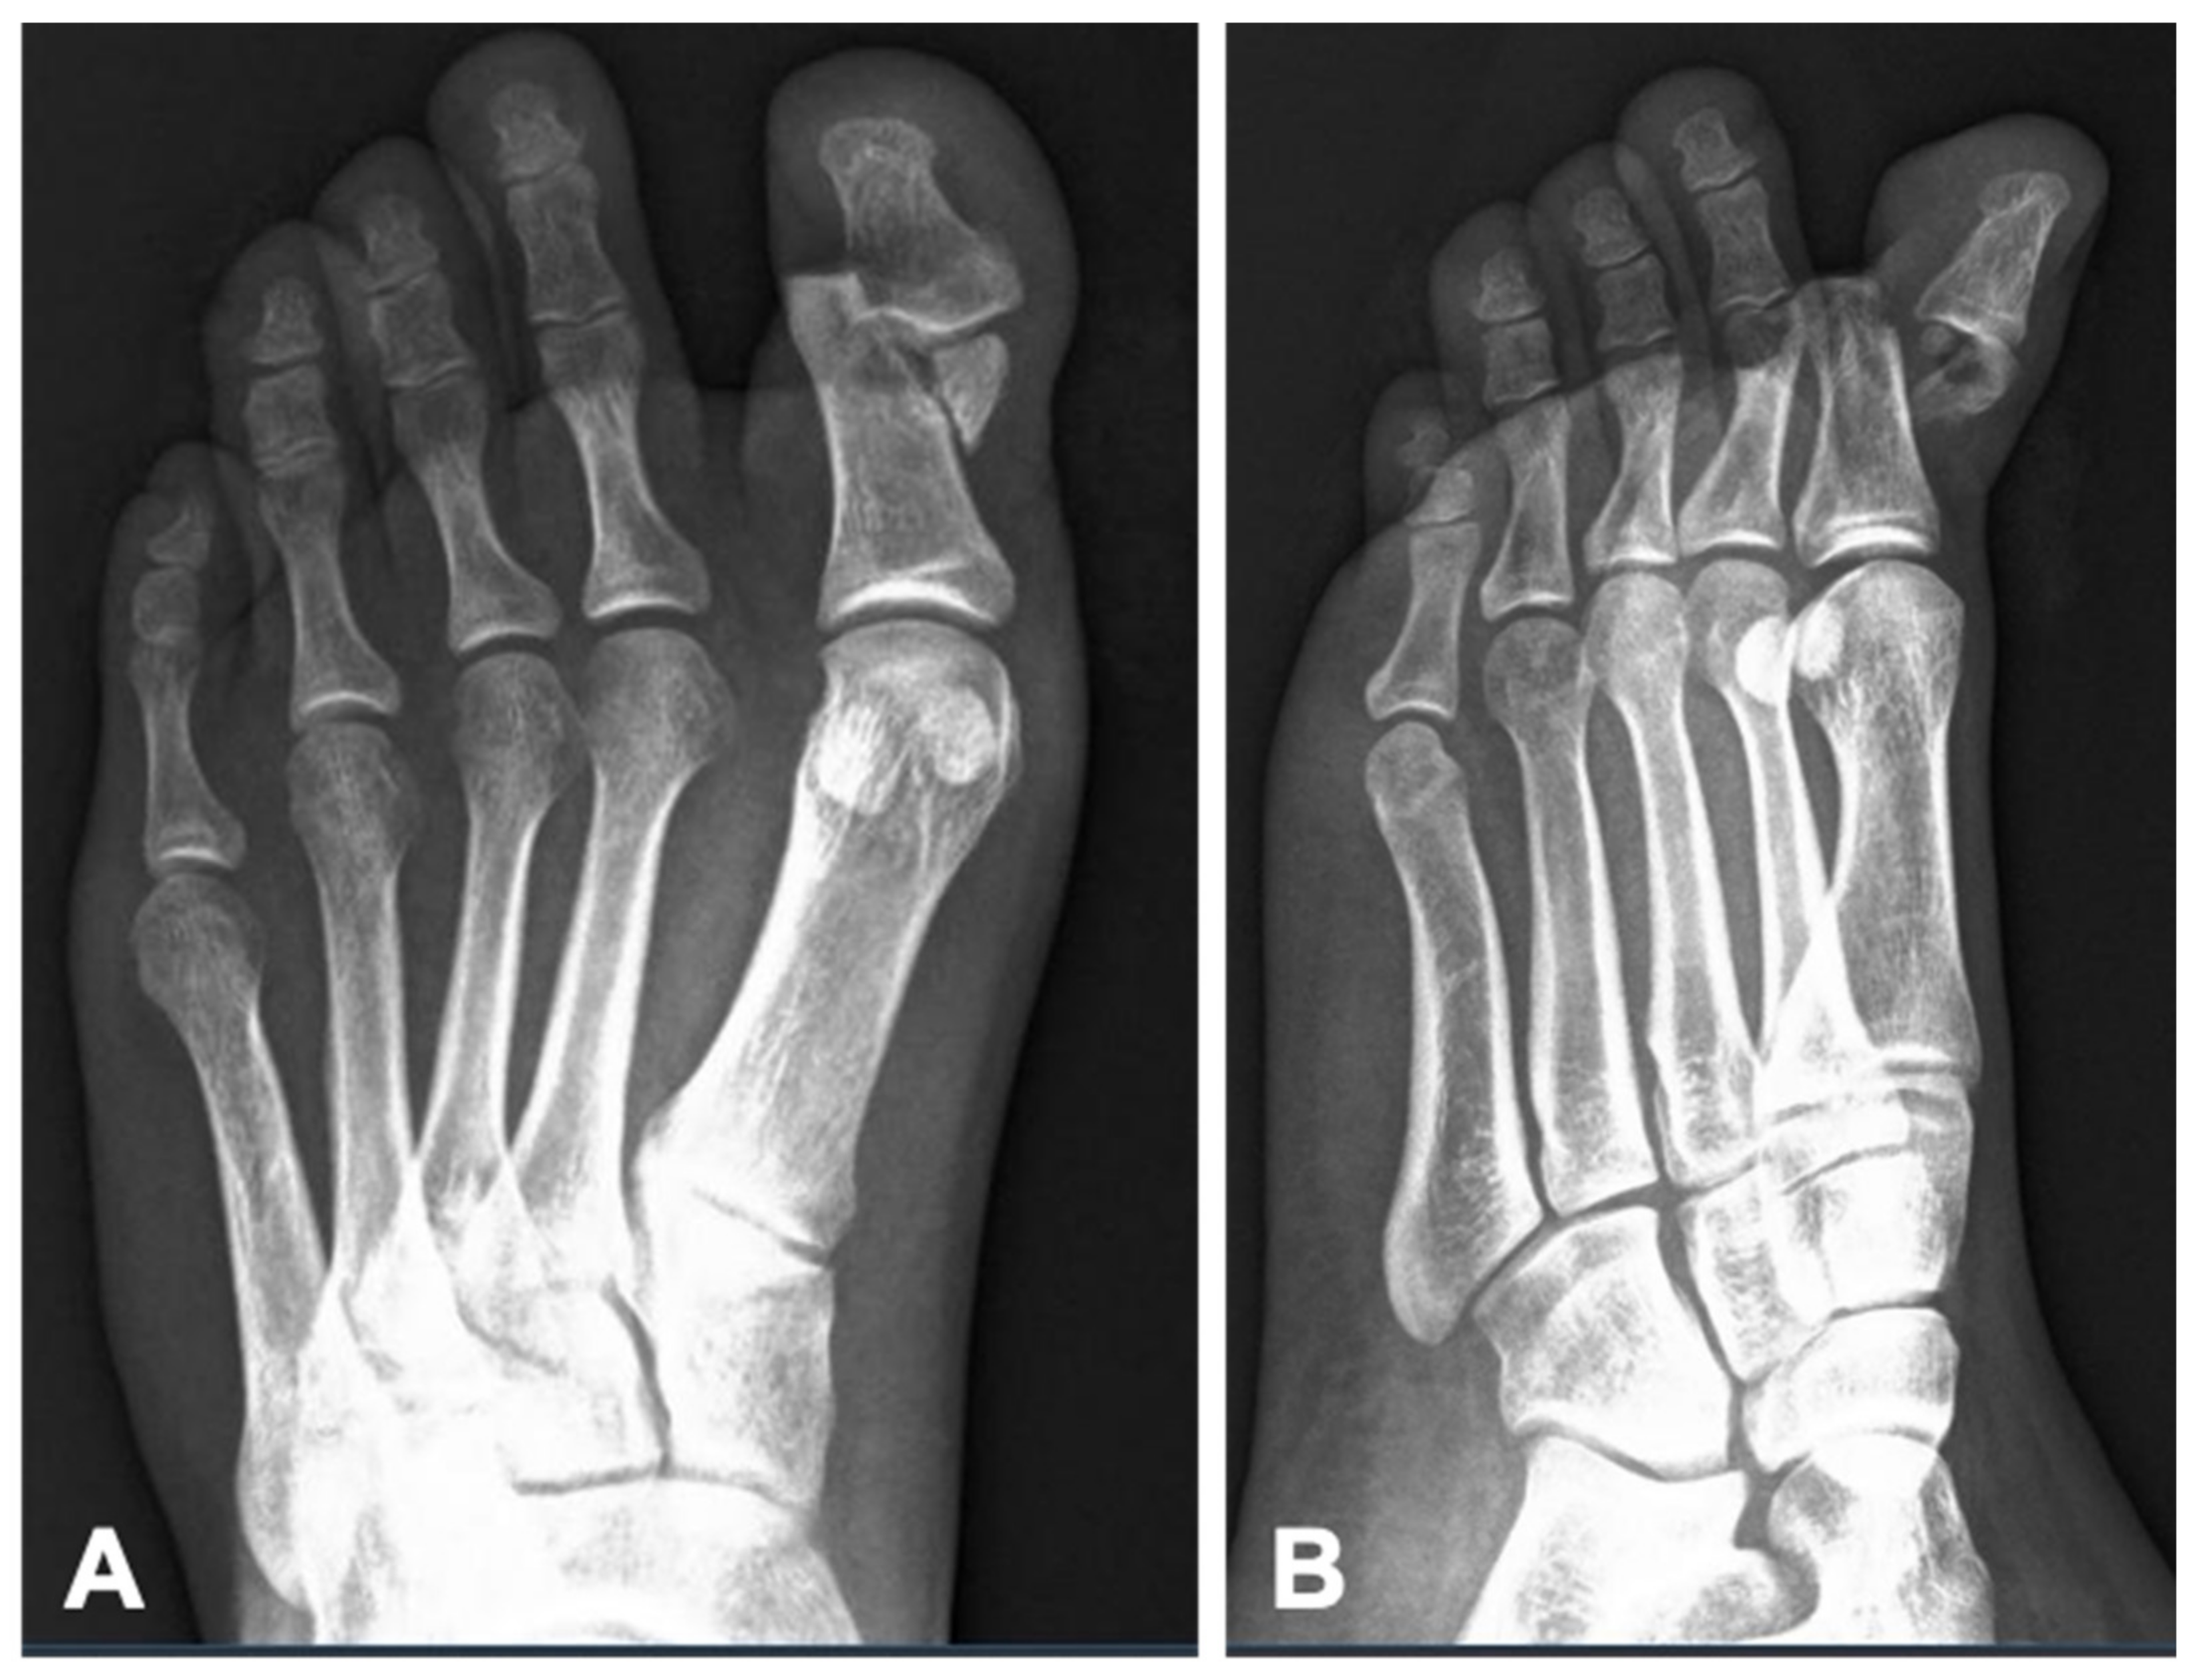

Informed consent was obtained from the patient for the publication of this case report. A 30-year-old female patient was admitted to the emergency department following a motor vehicle accident in which her left foot was trapped beneath a motorized vehicle. Clinic and radiographic evaluation revealed an open fracture of the proximal phalanx of the left hallux with 1 cm long skin cut, extending into the interphalangeal joint, accompanied by joint dislocation (

Figure 1).

After needle placement and proper irrigation and debridement, the layers were sutured anatomically, and a short-leg splint in neutral position was applied. Control radiographs confirmed proper anatomical alignment of the fracture (

Figure 2). The patient was discharged and scheduled for weekly follow-ups after prescription of amoxicillin clavulanic acid 1 g twice a day. The hypodermic needles were removed during the fourth week in the outpatient clinic and passive range of motion exercises and weight bearing were begun gradually. After 6 weeks, radiographs showed fracture union (